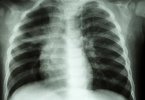

复张性肺水肿是罕见的特定条件下发生的急性肺损伤,是由什么原因引起的肺萎缩后发生的急性肺水肿。有些患者患有不同程度的低氧血症,有些严重的患者患有复发性低血压、休克症状,死亡率达到20%。病人的治疗方法各不相同,需要强调强烈的有效性和个性化,早期通过呼吸器的支持和纠正血流动力学障碍达到治疗效果。

肺毛细血管透过性强可能是复张性肺水肿的主要原因。有些患者在生病前有气胸、胸腔积液、胸腔内巨大肿瘤等症状,容易引起侧肺萎缩。由于负压抽吸迅速排除大量胸腔积液或积气,造成胸部毛细血管长期性萎缩缺氧损害,造成肺突然复张引起肺循环异常的病理状态。一般来说,血管内外压差增大,毛细血管内的血液渗透到肺间质和肺本质,出现肺水肿、肺淤血、肺动脉高压等重病。一般经胸腔闭式引流或肿瘤切除术,解除对肺的压迫,使萎缩的肺复发。患病者很容易会在短时间内出现急性的肺水肿问题,并且病死率达到20%左右。